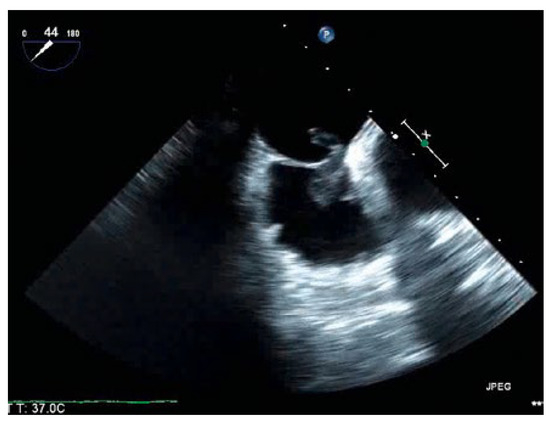

An 88-year-old man with a history of transient ischaemic attack, chronic kidney disease and primary hypertension presented with dyspnoea and was found to have large bilateral pulmonary emboli on a computedtomography angiogram of the chest [...]